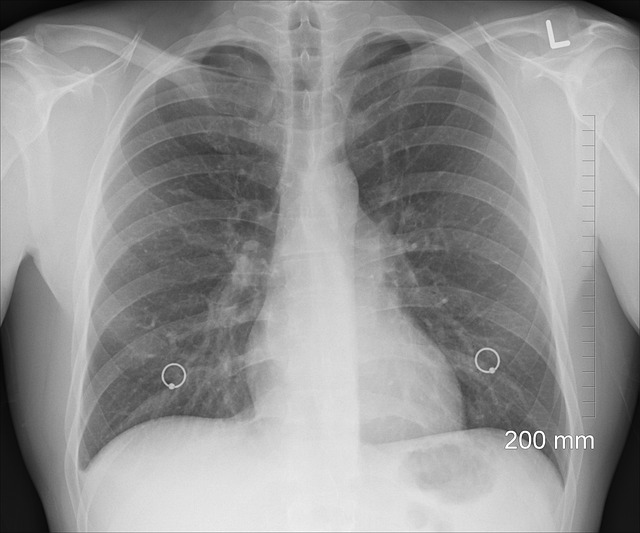

2. 폐암 – 증상이 없어서 더 위험한 암

폐암이란?

폐암은 폐에 악성 종양이 발생하는 질환으로, 초기에 증상이 거의 없어 '조용한 암'이라고도 불립니다. 한국에서는 폐암이 사망률 1위 암으로, 조기 발견이 매우 중요합니다.

폐암의 증상

초기에는 증상이 거의 없지만, 진행되면 다음과 같은 증상이 나타날 수 있습니다.

- 지속적인 기침과 가래

- 숨 가쁨과 가슴 통증

- 피가 섞인 가래

- 이유 없는 체중 감소

폐암 예방법

- 저선량 CT 검사: 고위험군(흡연자, 가족력 있는 경우)은 정기적으로 폐암 검사를 받아야 합니다.